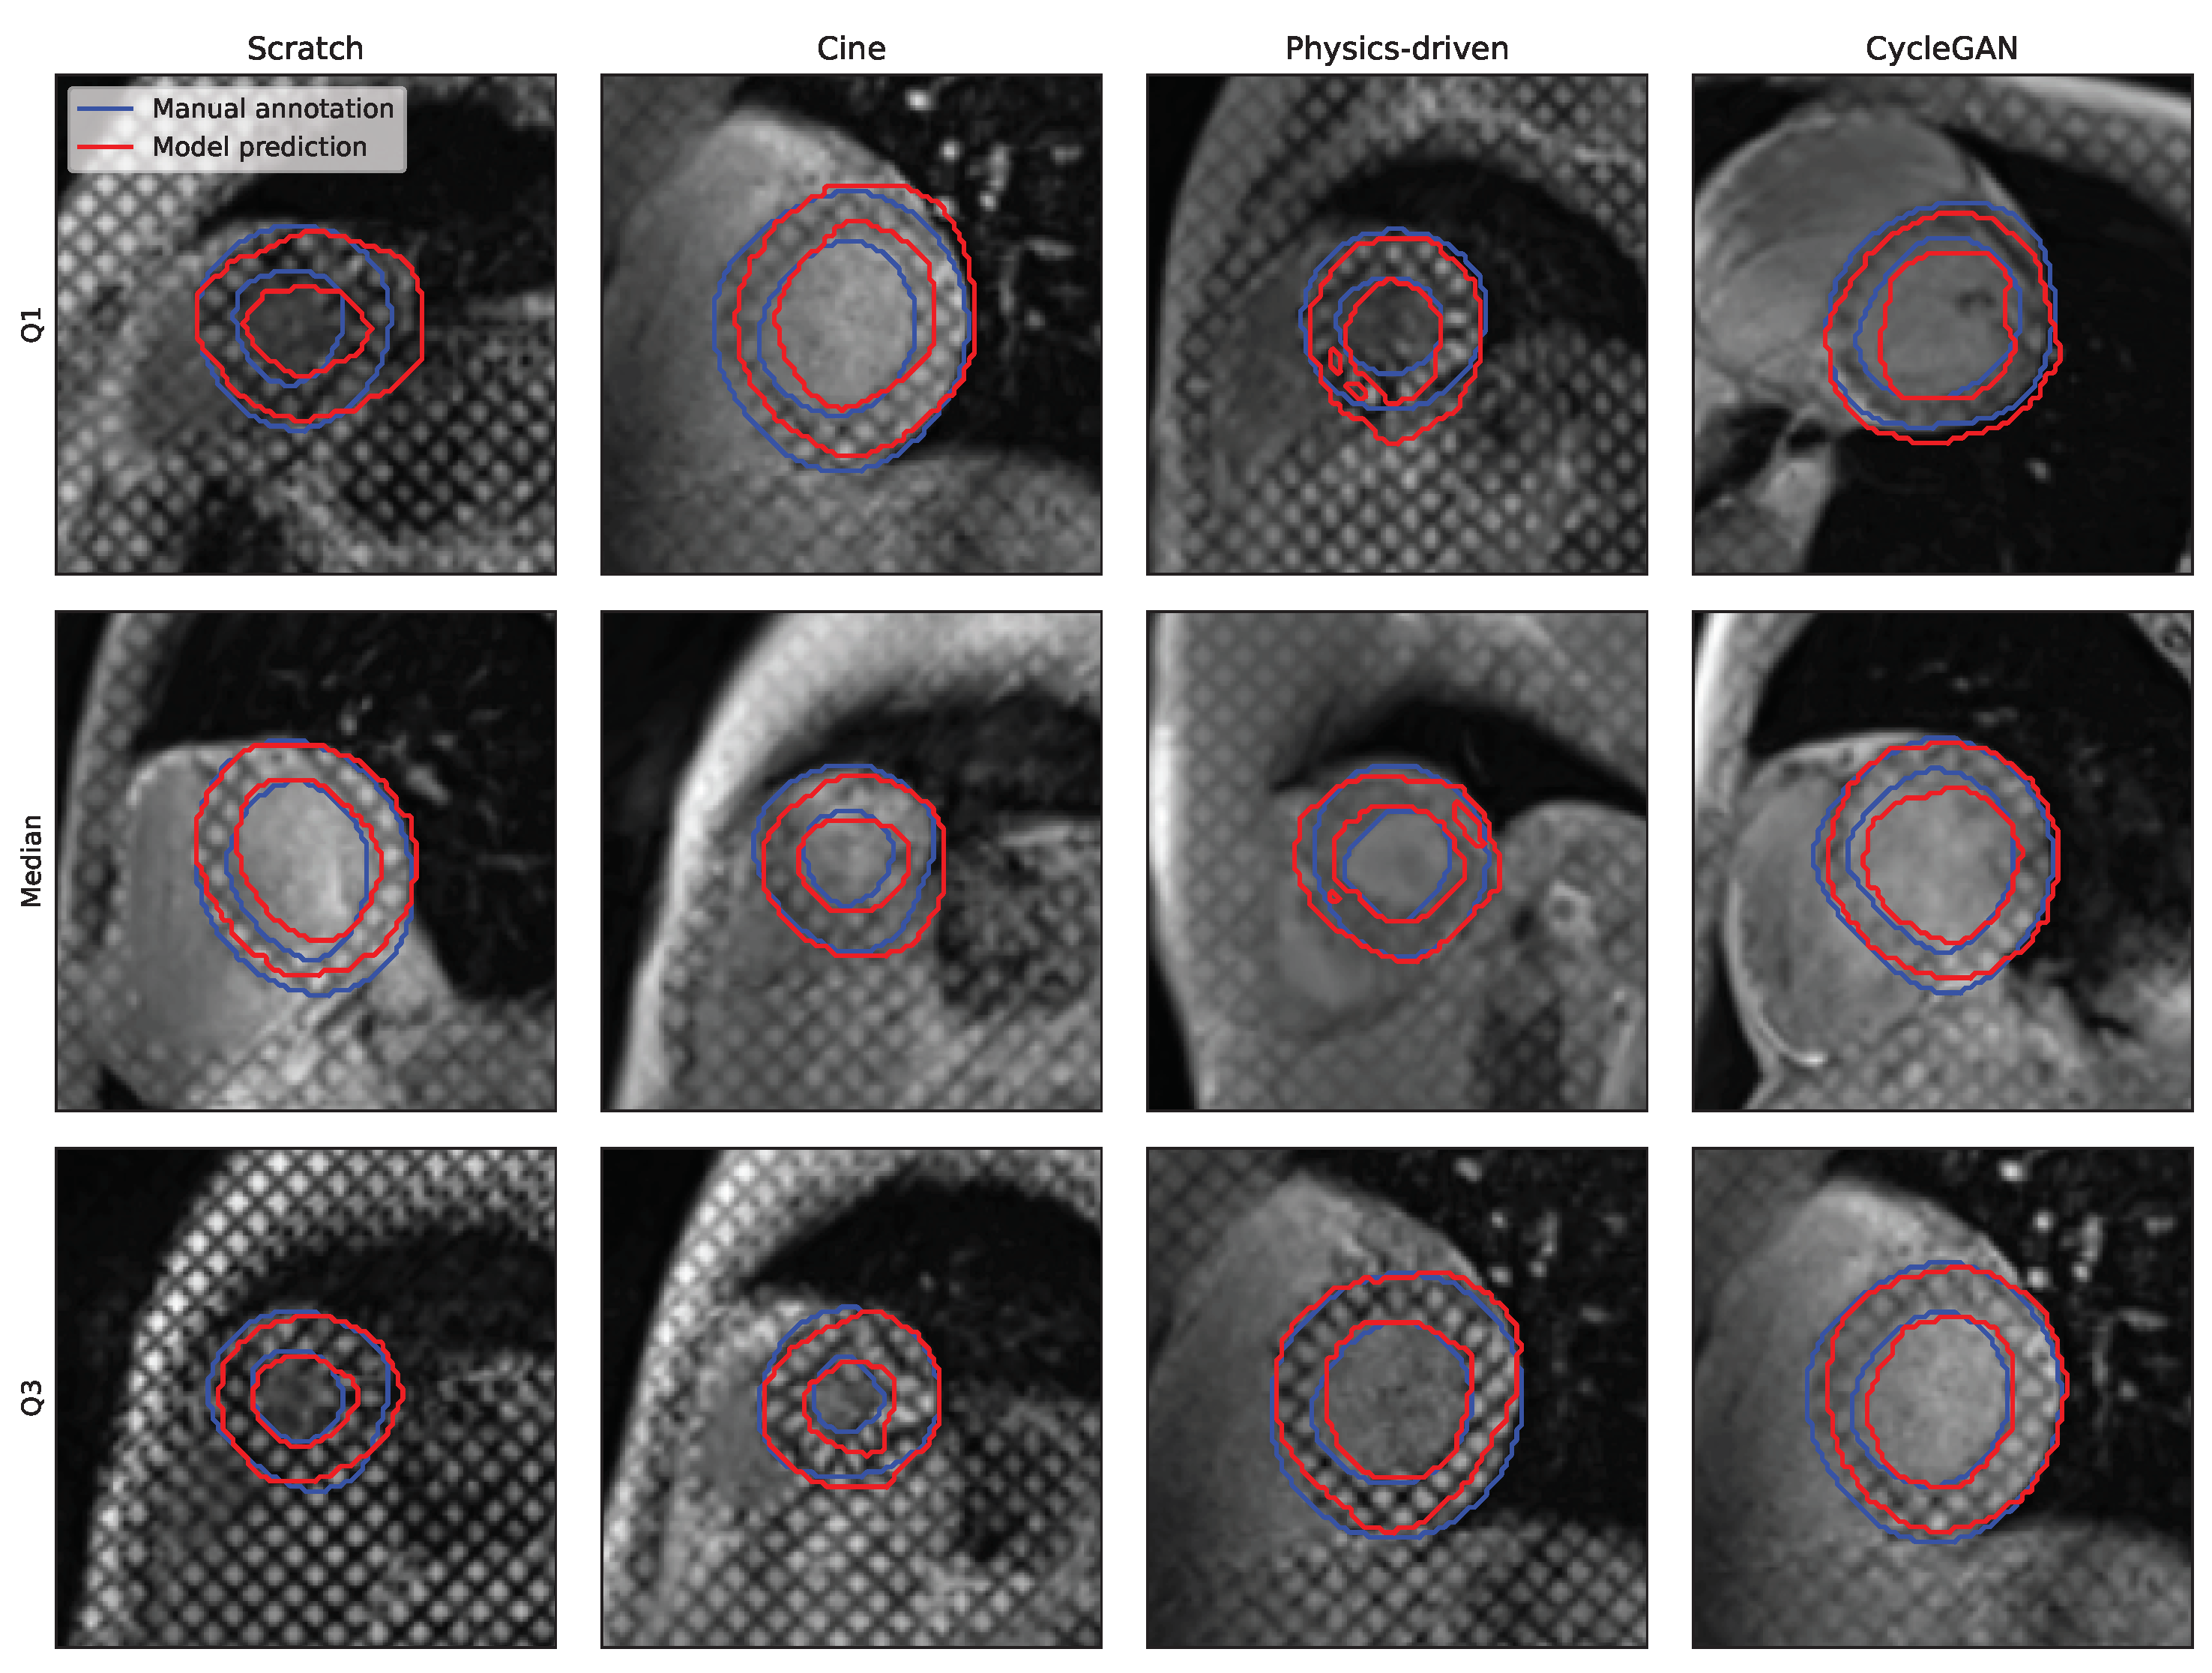

3.2.2. Training Strategies

3.2.3. Acquisition Time-Frame

4.1. Analysis of the Cine to Tagged Image Transformation Models

4.2. Analysis of the DL-Based Segmentation Network